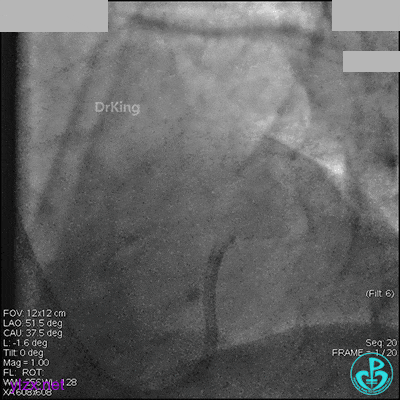

冠脉造影

入院次日冠脉造影显示粗大左主干末端中度狭窄,前降支开口严重狭窄,回旋支与前降支角度大,弥漫性长病变,严重狭窄,粗大右冠脉近中段弥漫性中重度狭窄。由于病变复杂,造影结束后先下台,择期再行介入治疗。